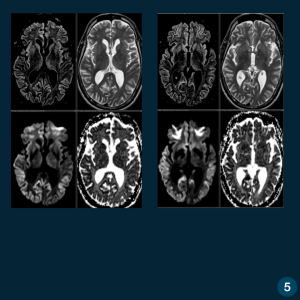

Caso do Dia – Encefalopatia espongiforme